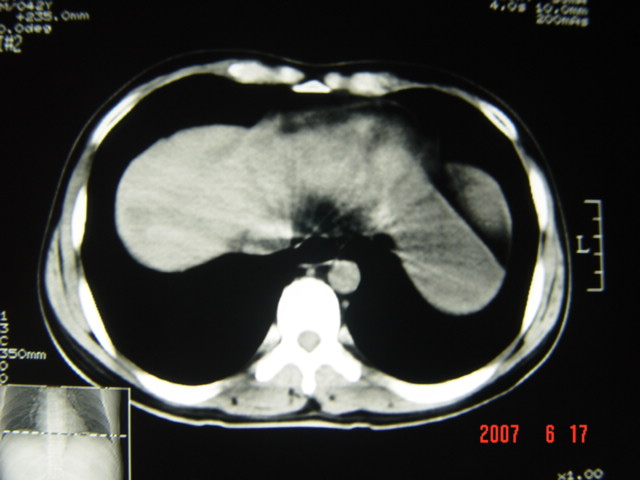

[br][br]以下是引用lkc8963在2007-6-17 13:32:00的发言:[br]完全支持邓主任意见:降/乙交界部占位性病变伴不全梗阻.做个增强或者be可能更好.